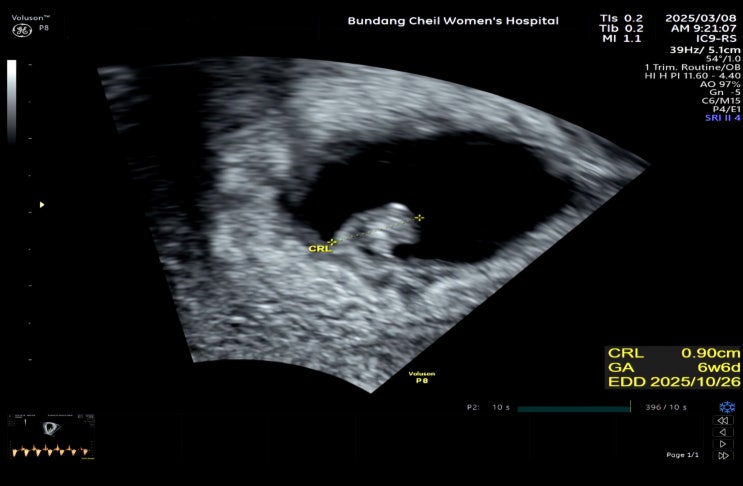

[5주-7주]아기집/난황/심장소리/입덧증상

동결 6차/ 시험관 8차 모자이시즘배아+검사안한 5일배아중 어떤게 착상했는지는 모르지만 오랜 기다림만에 ...